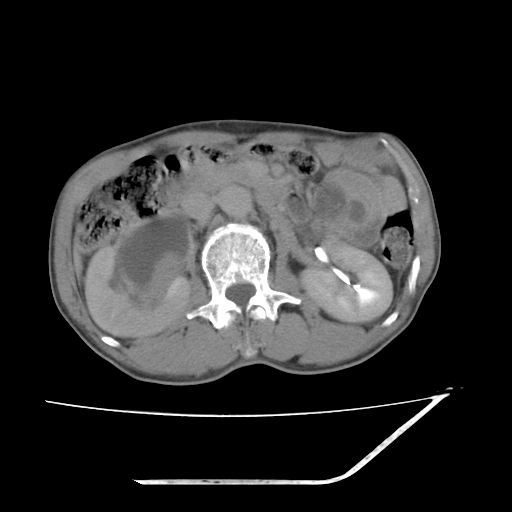

平扫

考虑右肾盂癌,肾动脉受侵,右肾功能减退,右肾盂输尿管积水,管壁增厚,考虑种植转移,应该把下面扫完的

支持右侧肾盂癌伴肾静脉瘤栓形成可能性大,右肾结石.肝右叶后段低密度影,不除外转移.

右肾盂旁ca并肾静脉瘤栓形成/肾功能降低。

右肾结石。

右肾盂癌,肾动脉受侵,右肾盂输尿管积水,管壁增厚,考虑种植转移

支持 右侧肾盂癌伴肾静脉瘤栓形成可能性大,右肾结石;肝右叶后段低密度影,不除外转移。

1.右侧肾盂癌伴肾盂积水。

2.肾脏功能减退,原因有:(1)肾动脉受侵。(2)肾静脉受侵(3)肾积水,等。本例,肾动脉显影较好,但受压明显;肾静脉无明显显示,受压或静脉癌栓,下腔静脉腔内未见明显充盈缺损。

3.右侧上段输尿管扩张,原因:(1)积水所致;(2)种植。